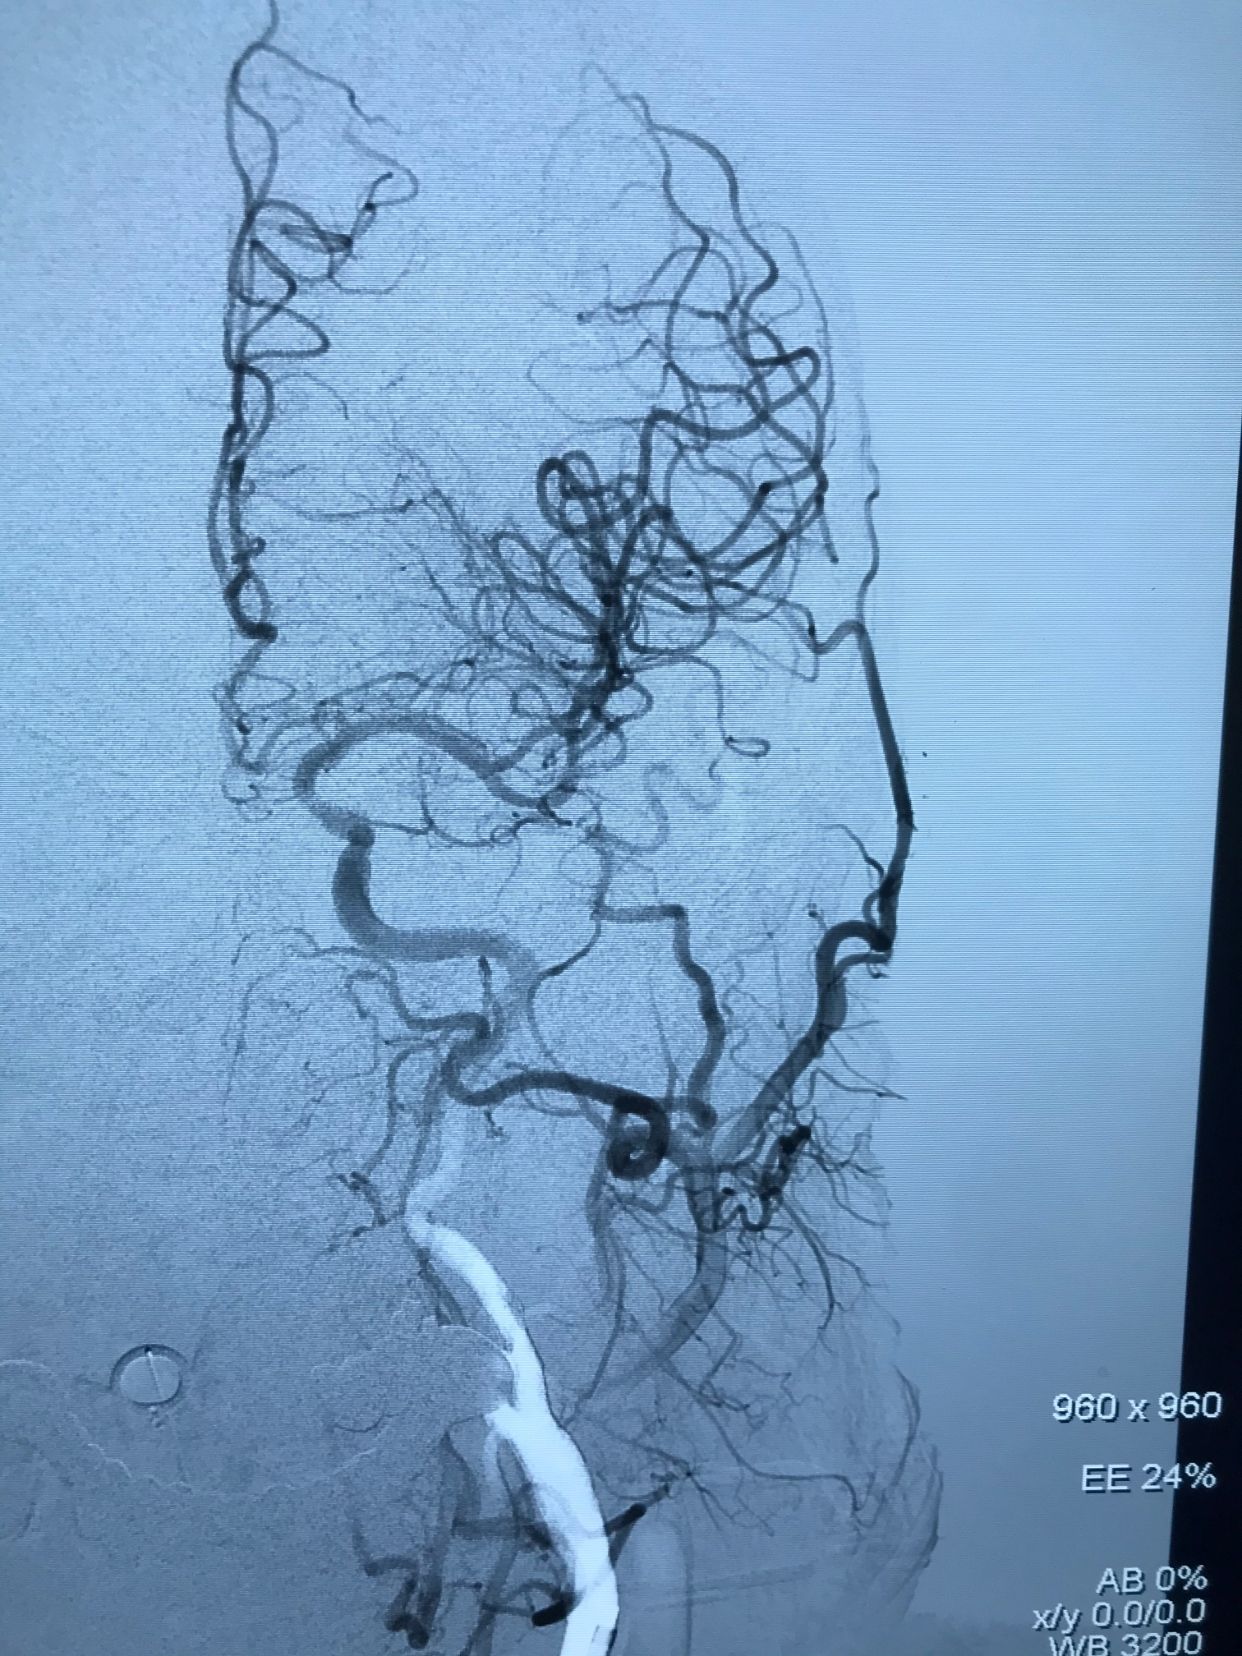

入院后先静脉溶栓,溶栓期间症状加重,右侧肌力持续下降,逐渐出现意识障碍!急诊造影显示左侧颈内动脉开口重度狭窄基础上急性闭塞!

术后正位造影,颅内血管显影良好!

术后侧位造影!